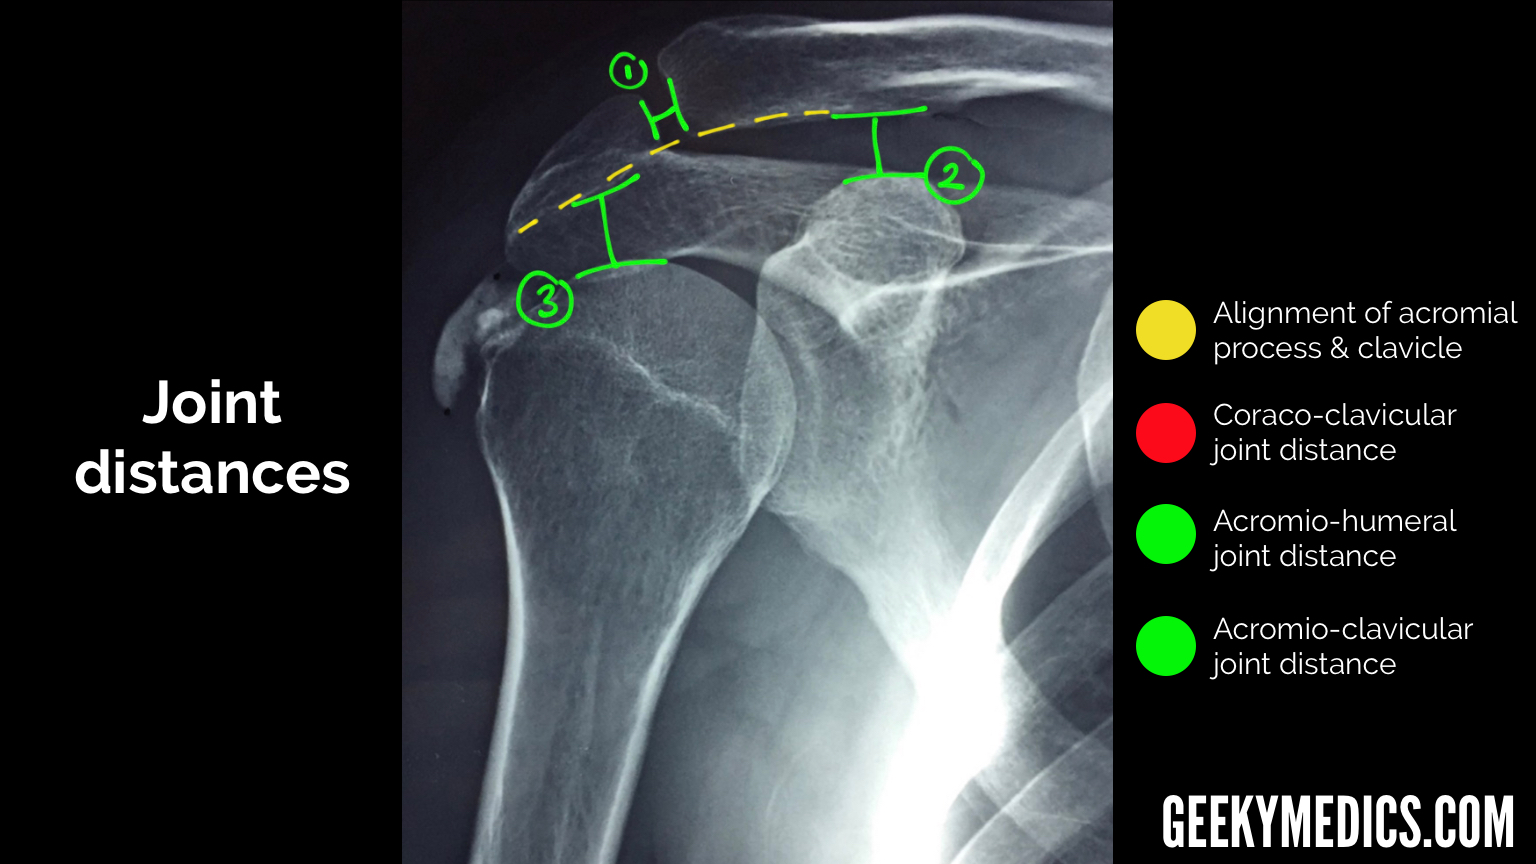

From geekymedics.com

Shoulder Xray Interpretation Radiology Geeky Medics Normal Right Shoulder X Rays Glenohumeral joint alignment is normal with. A video tutorial in interpreting radiographs of the shoulder joint and surrounding areas. A normal shoulder x ray will demonstrate the bones of the shoulder to have expected normal appearance. 3 articles feature images from this case. 206k views 11 years ago. Scroll or drag your finger down to reveal the radiographic anatomy for. Normal Right Shoulder X Rays.

Shoulder Xray Interpretation Radiology Geeky Medics Normal Right Shoulder X Rays This is the second video. A normal shoulder x ray will demonstrate the bones of the shoulder to have expected normal appearance. Glenohumeral joint alignment is normal with. Medical imaging anatomy course >> learn more from the case: 206k views 11 years ago. A video tutorial in interpreting radiographs of the shoulder joint and surrounding areas. The shoulder series is. Normal Right Shoulder X Rays.